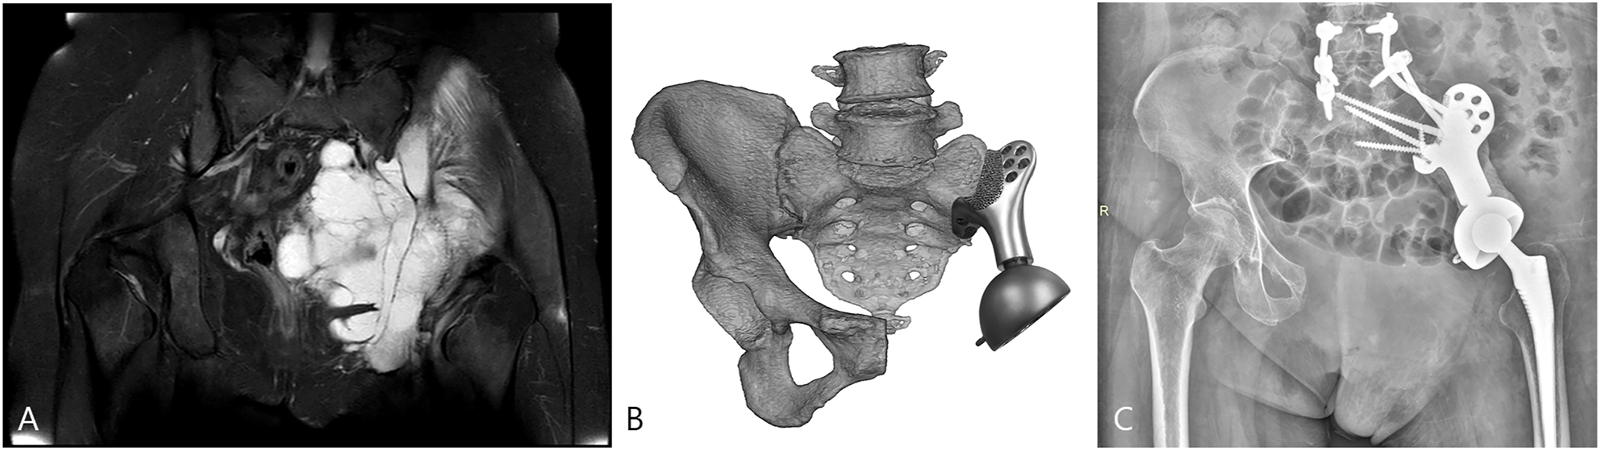

All patients were alive at the latest follow-up of 16.6 ± 7.5 months. Two patients had wound healing disturbance at the crossing site of the T-shaped incision attributable to excessive ligation of the terminal branch of the superior gluteal artery encompassing the tumor. One of the patients (case 1) received three cycles of irrigation and debridement, followed by a second-stage flap transfer. The patient experienced a recurrence at 16 months after surgery. This was followed by palliative tumor resection and implantation of radioactive 125I seeds. Multiple surgeries and prolonged bed rest impeded rehabilitation and resulted in inferior limb function. At 8 months after surgery, one patient (case 2) had a local recurrence which was treated with expanded resection and was diagnosed with pulmonary metastasis at 3 months before the latest follow-up. No signs of component breakage or aseptic loosening was observed (Figure 7), and the ability to ambulate was restored with a MSTS-93 score of 19.5 ± 2.9.

FIGURE 7

The patient (case 3) with the highest BMI was selected for FE analysis. (A) Preoperative magnetic resonance imaging (MRI) showed the involvement of the sacroiliac joint. (B) The surgery simulation that fitting the sacral tray onto the ventral sacrum. (C) The postoperative X-ray at the latest follow-up.